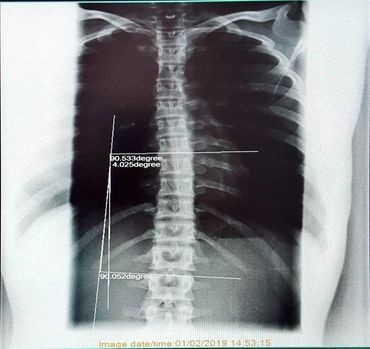

A 15 year old, competitive, cheerleader came in to the clinic with upper and lower back pain after having someone fall on them from a height during a practice. Upon examination and an x-ray of their thoracic spine (mid back) we measured a curve of 24 degrees. After 6 short months of chiropractic treatment and Myopulse, and a re-examination and x-ray the curve reduced to 4 degrees and is no longer classified as scoliosis! Both the patient and their family are happy with the decrease in tightness and pain and the patient's improved performance on their cheer squad!